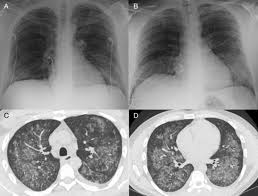

When To Rule Out Covid 19 How Many Negative Rt Pcr Tests Are Needed Sciencedirect